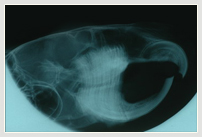

Zahnröntgen Chinchilla